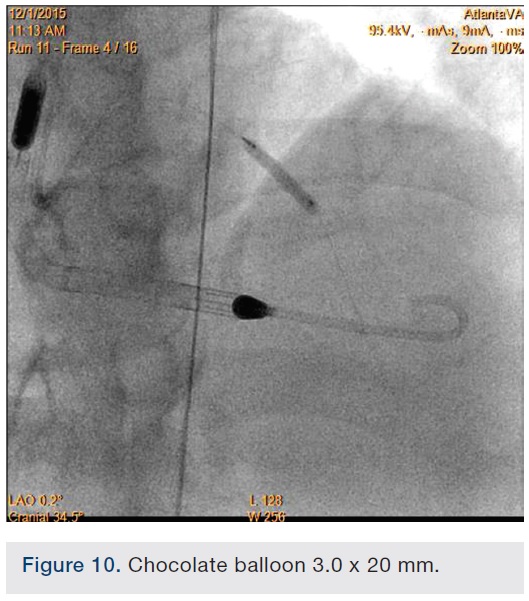

Following successful completion of the peripheral phase, it was felt that a 4-week period was necessary for the iliac stent to heal somewhat (especially since we planned to place a 14 French Cook sheath through it). We then moved on to the coronary phase of this procedure. Bilateral groins and the right wrist were prepared and draped in the usual sterile fashion. Using micropuncture technique with fluoroscopic verification of needle entry into the left CFA at the upper quadrant of the femoral head, a 6 French sheath was placed in the left CFA. The existing left femoral arterial sheath was removed, and the arteriotomy was pre-closed with a single Perclose device (Abbott Vascular). The arteriotomy was then serially dilated with 10, 12 and 14 French dilators, and a 14 French, 30 cm Cook sheath was placed successfully in the left common femoral artery. Following therapeutic anticoagulation with intravenous heparin, a regular J-wire and a 6 French pigtail catheter were used to cross the aortic valve, and the catheter was used to exchange the J wire for the 0.018-inch Platinum Plus wire (Boston Scientific). The Impella CP (3.5) percutaneous left ventricular assist device (LVAD) (Abiomed) was inserted into the left ventricle over the Platinum Plus wire (Figure 8). The Impella was then activated and good flows were verified. Right radial artery access was obtained and a PB 3.0 7.5 French sheathless guide system (Asahi Intecc) was used to engage the left main coronary artery. The LAD was wired uneventfully using a Runthrough wire (Terumo) via a 1.25 x 6 mm over-the-wire (OTW) Sprinter balloon (Medtronic). This was then exchanged for a Viper wire (CSI). Orbital atherectomy of the proximal LAD lesion was performed with excellent results (80,000 rpm x 4 passes, 120,000 rpm x 2 passes) (Figure 9). The LAD wire was then exchanged for a Runthrough wire and the left circumflex (LCX) was wired with a BMW wire. Following plaque modification with orbital atherectomy, predilation of LAD was performed with 3.0 x 20 mm Chocolate Balloon (QT Vascular Ltd) (15 atmospheres x 60 seconds and 15 atmospheres x 30 seconds) (Figure 10) with an excellent result and no dissection (Figure 11). A 3.5 x 38 mm Promus stent (Boston Scientific) (14 atmospheres x 30 seconds) was placed from the left main into the proximal LAD lesion ensuring adequate coverage. The jailed LCX wire was recovered and re-placed in the LCX through the struts of the newly placed LM-LAD stent (Figure 12). Predilation of the LCX ostium was performed with a 2.5 x 8 mm Glider balloon (QT Vascular Ltd) (14 atmospheres x 25 seconds). The mid LAD was stented (ensuring overlap with proximal stent) with 3.0 x 16 mm Promus stent (16 atmospheres x 25 seconds). A final kissing balloon inflation of the LAD/LCX with an NC Sprinter 2.5 x15 mm balloon (Medtronic) into the LCX and a NC Sprinter 3.5 x12 mm balloon into the LAD was performed, with up to 16 atmospheres x 20 seconds on both (Figure 13). Final IVUS of the LM and LAD stent revealed excellent results and the LCX ostium looked excellent as well (Figures 14-16).

In our experience, there are significant synergies to be exploited between the CSI Diamondback atherectomy device and the Chocolate balloon (QT Vascular Ltd). The orbital atherectomy device works by shaving or sanding calcified areas of the artery and may sometimes leave calcified spicules in the vessel that can be optimally modified further with adjunctive Chocolate balloon angioplasty, thus enabling excellent stent expansion and apposition, allowing for decreased restenosis and thrombosis. The Chocolate balloon consists of a mounted nitinol constraining structure specifically designed for uniform, controlled inflation and rapid deflation, resulting in atraumatic dilatation without the need for cutting or scoring. Because of its novel design, it is able to enable focused force angioplasty from its “pillows” while allowing plaque channeling through its “grooves”.